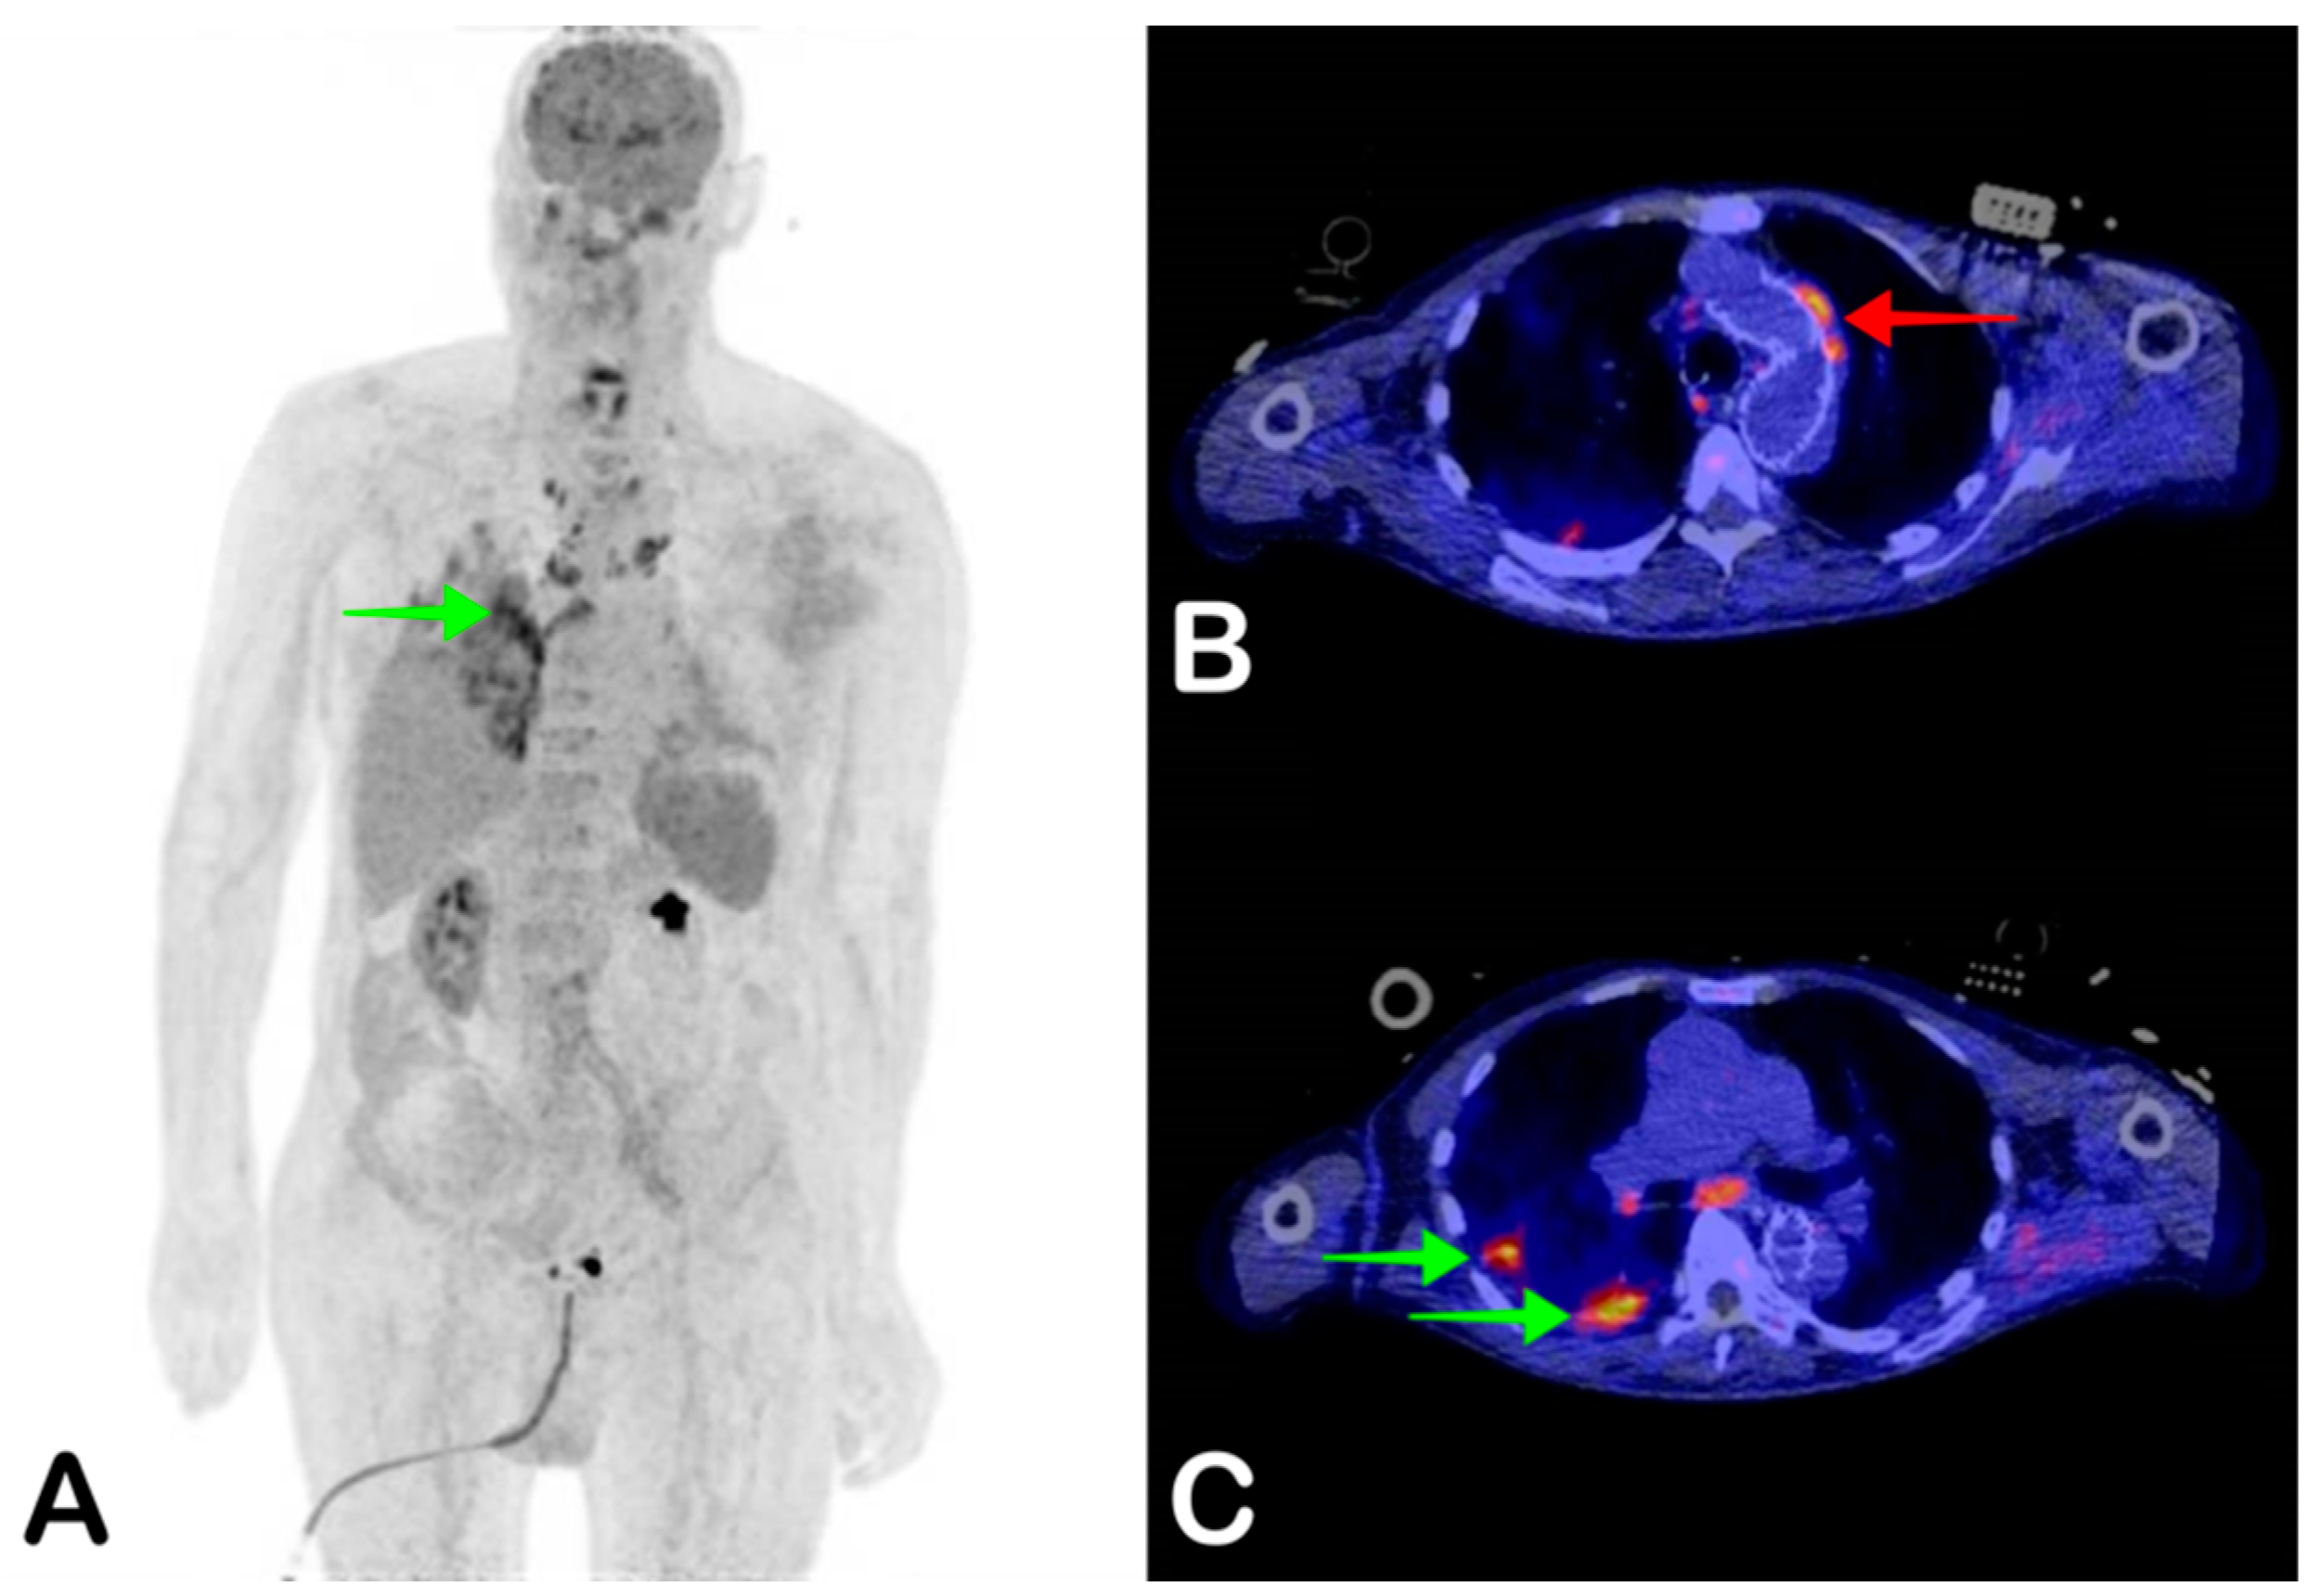

2.4. Vascular Graft Infection

- Wilson, W.R.; Bower, T.C.; Creager, M.A.; Amin-Hanjani, S.; O’Gara, P.T.; Lockhart, P.B.; Darouiche, R.O.; Ramlawi, B.; Derdeyn, C.P.; Bolger, A.F.; et al. Vascular Graft Infections, Mycotic Aneurysms, and Endovascular Infections: A Scientific Statement from the American Heart Association. Circulation 2016, 134, e412–e460. [Google Scholar] [CrossRef]

- Keidar, Z.; Nitecki, S. FDG-PET in Prosthetic Graft Infections. Semin. Nucl. Med. 2013, 43, 396–402. [Google Scholar] [CrossRef]

- Keidar, Z.; Engel, A.; Hoffman, A.; Israel, O.; Nitecki, S. Prosthetic Vascular Graft Infection: The Role of 18F-FDG PET/CT. J. Nucl. Med. 2007, 48, 1230–1236. [Google Scholar] [CrossRef]

- Saleem, B.R.; Pol, R.A.; Slart, R.H.J.A.; Reijnen, M.M.P.J.; Zeebregts, C.J. 18F-Fluorodeoxyglucose Positron Emission Tomography/CT Scanning in Diagnosing Vascular Prosthetic Graft Infection. BioMed Res. Int. 2014, 2014, 1–8. [Google Scholar] [CrossRef]

- Chakfé, N.; Diener, H.; Lejay, A.; Assadian, O.; Berard, X.; Caillon, J.; Fourneau, I.; Glaudemans, A.W.; Koncar, I.; Lindholt, J.; et al. Editor’s Choice—European Society for Vascular Surgery (ESVS) 2020 Clinical Practice Guidelines on the Management of Vascular Graft and Endograft Infections. Eur. J. Vasc. Endovasc. Surg. 2020, 59, 339–384. [Google Scholar] [CrossRef]